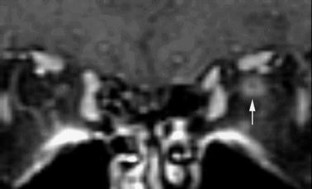

Optic nerve sheath dilatation or gadolinium-enhancement on magnetic resonance imaging in acute optic neuritis have been previously reported but have been thought to be rare occurrences. This study recruited 33 patients with acute unilateral optic neuritis. All had their optic nerves imaged with fat-saturated fast spin-echo (FSE) imaging, and 28 had imaging before and after triple-dose gadolinium-enhanced fat-saturated T1-weighted imaging. Follow-up imaging was performed on 20 patients (15 following gadolinium). A dilated subarachnoid space at the anterior end of the symptomatic optic nerve on FSE imaging was seen in 15/33 cases. In three of these cases, dilatation was visible on short-term follow-up. Optic nerve sheath enhancement was seen in 21/28 cases acutely: seven at the anterior end of the lesion only, five at the posterior end only and nine at both ends. Optic sheath enhancement was seen in 13 patients on follow-up. This study suggests that optic nerve sheath dilatation on FSE images and optic nerve sheath enhancement on triple-dose gadolinium-enhanced images are common findings in acute optic neuritis. Optic nerve sheath dilatation may be due to inflammation of the optic nerve, with its associated swelling, interrupting the communication between the subarachnoid space of the diseased optic nerve and the chiasmal cistern. Optic nerve sheath enhancement suggests that meningeal inflammation occurs in optic neuritis, in agreement with pathological studies of both optic neuritis and multiple sclerosis.